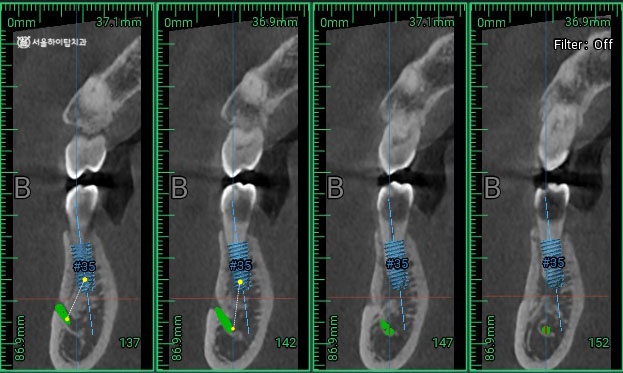

이 과정에서 CBCT 데이터를 기반으로 한 가상 시뮬레이션을 통해

식립 각도와 깊이, 보철적 중심 위치를 사전에 설계할 수 있습니다.

현재 하치조신경과의 거리는 괜찮습니다.

또한 잔존골의 양과 bone level 도 일정 수준 이상 나와주기 때문에

추가적인 골 이식 없이 임플란트를 식립할 수 있는 소견입니다.